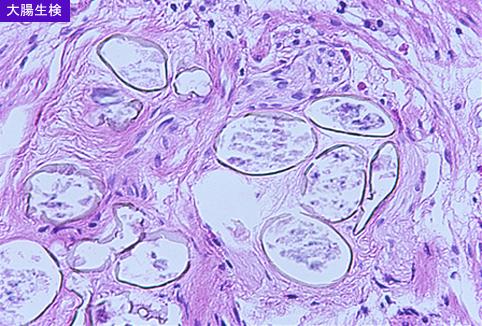

粘膜下の虫卵の強拡大像(X100,HE)である。

疾患(病理主体)の分類寄生虫疾患/その他

部位(臓器別)大腸/盲腸

検査方法ミクロ

病変の最大径(ミリ)1〜9